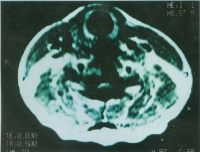

CT检查[编辑 | 编辑源代码]

在CT扫描图上胰假性囊肿为边缘光滑的圆形或卵圆形密度均匀减低区。如CT检查显示有气液平面,说明有感染性脓肿形成。